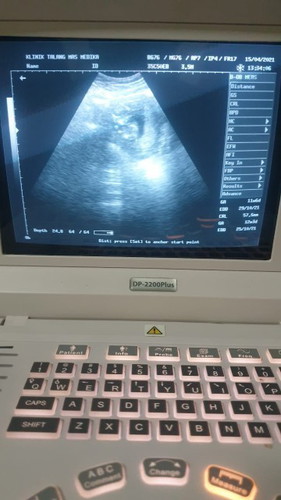

Alhamdulillah sehat selalu syg di dalem perut itunganUSG yg di komputer 12w tapi itungan sya udh 14w

Yang penting sehat selalu di berikan kelancaran sampai persalinan nanti amin allahuma amin